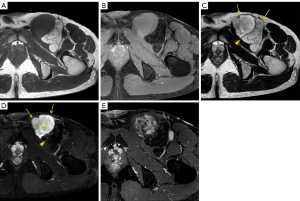

Representative MRI images are shown in Figures 1-3. Corresponding histopathological findings of the lesions in Figures 1,3 are shown in Figures 4,5, respectively.

In cases of fat-containing tumors, the T1WI signal intensity reflects fat content, which is diagnostically significant. Earlier studies have categorized ASPLT T1WI signal intensity into the following three groups: (I) high; (II) mixed high and low; and (III) low (6). However, since some high T1WI signals may be attributed to hemorrhage or myxoid components (8), this study focused on evaluating fat content using selective fat suppression techniques instead of T1WI signal intensity. Fat content varied widely, with an average score of 1.74 and median score of 1, indicating a tendency toward low fat content in the cases assessed. Histopathological examination similarly confirmed a tendency toward low fat content, with findings consistent with imaging in many cases (Figures 4A,5A). Furthermore, fat was not only interspersed within the nonfatty components but also often present as distinct nodules, which corresponded well with the MRI findings.

Regarding nonfatty components, T2WI high-signal areas appeared in 18 cases (94.7%), with 17 cases (89.5%) showing high-signal areas covering approximately 25% of the lesion. T2WI low-signal septa were observed in all cases. Contrast enhancement appeared in 15 of 16 cases (93.8%), predominantly in T2WI high-signal areas and in T2WI low-signal areas in 12 cases (75.0%). Histologically, abundant collagen fibers and myxoid material were observed in these lesions (Figures 4C-4E,5C-5E), which corresponded well with the signal characteristics on T2WI. Specifically, T2WI low-signal areas were considered to reflect collagen fibers, whereas high-signal areas were attributed to myxoid components. However, no discernible histological differences were observed that could account for the variation in contrast enhancement (i.e., moderate in Figure 4 and faint in Figure 5).

Other findings included well-defined margins in eight cases (42.1%) and capsular structures in 17 cases (89.5%). Margins have been reported to be indistinct owing to peripheral infiltration (2,4). In our pathological analysis as well, capsule-like structures were observed at the tumor margins; however, tumor infiltration beyond these structures was also identified in some areas (Figures 4B,5B). This suggests that the capsules observed on MRI may not represent true tumor capsules, but rather so-called “pseudocapsules” formed by compression or reactive changes in the surrounding tissue.

Edema-like signals appeared in two cases (10.5%) (positive, Figure 1; negative, Figure 3). However, corresponding tumor infiltration was not observed histologically (Figure 4C), suggesting that these findings were unlikely to affect surgical handling or postoperative outcomes.